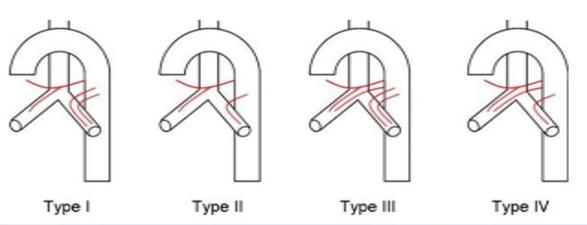

the bronchial arteries come from where? what will you commonly see with these?

from the aorta

you will see them coming from variable pathways from the aorta

in this person, what bronchial arteries can you point out?

you can point out the right bronchial artery and then on the other side, the left superior bronchial artery and the left inferior bronchial artery both going to the same bronchi tube on bottom